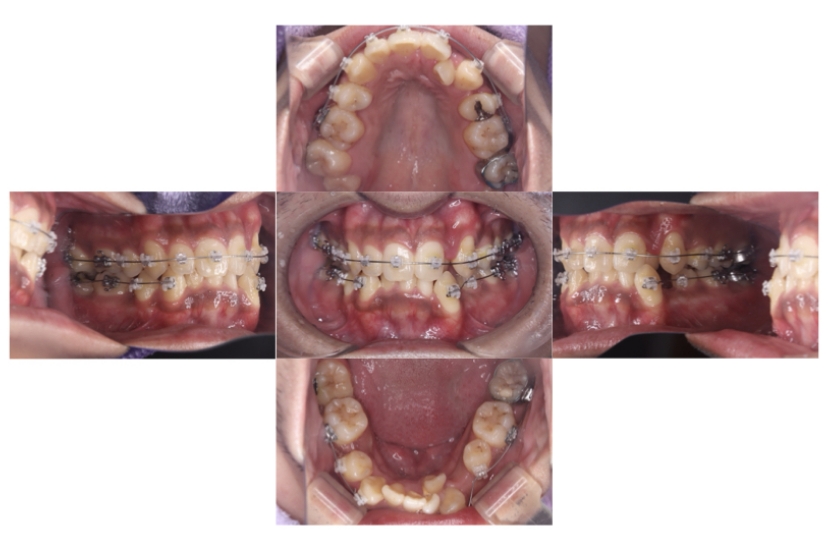

BEFORE

治療経過

AFTER

症例8

叢生

抜歯

ブラケット矯正

上下顎叢生(上下の前歯のガタガタ)のケースです。

装置はラビアル(上下表側)で、上下顎の小臼歯を4本抜歯を行っています。抜歯したスペースを使って、上下の前歯の後方移動と叢生(ガタガタ)の改善を行っています。

主訴 歯並びが悪く、舌を噛んでしまうのを治したい。

年齢・性別 27歳 男性

お住まいの地域 東京都大田区

治療方針 抜歯スペースを利用して上下前歯の叢生(ガタガタ)の改善

抜歯部位 上下顎左右第一小臼歯

使用装置 ラビアル(上下表側)、顎間ゴム

治療期間 3年1か月

治療回数 30回

リテーナー クリアリテーナー